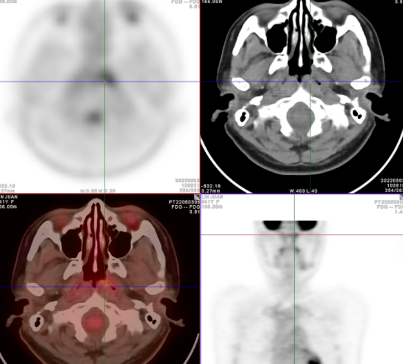

Fig.1

18F-FDG PET/CT 显像图像

Fig.2

右侧咽旁间隙见一FDG摄取异常增高淋巴结 ,SUVmax6.6,短径约9mm